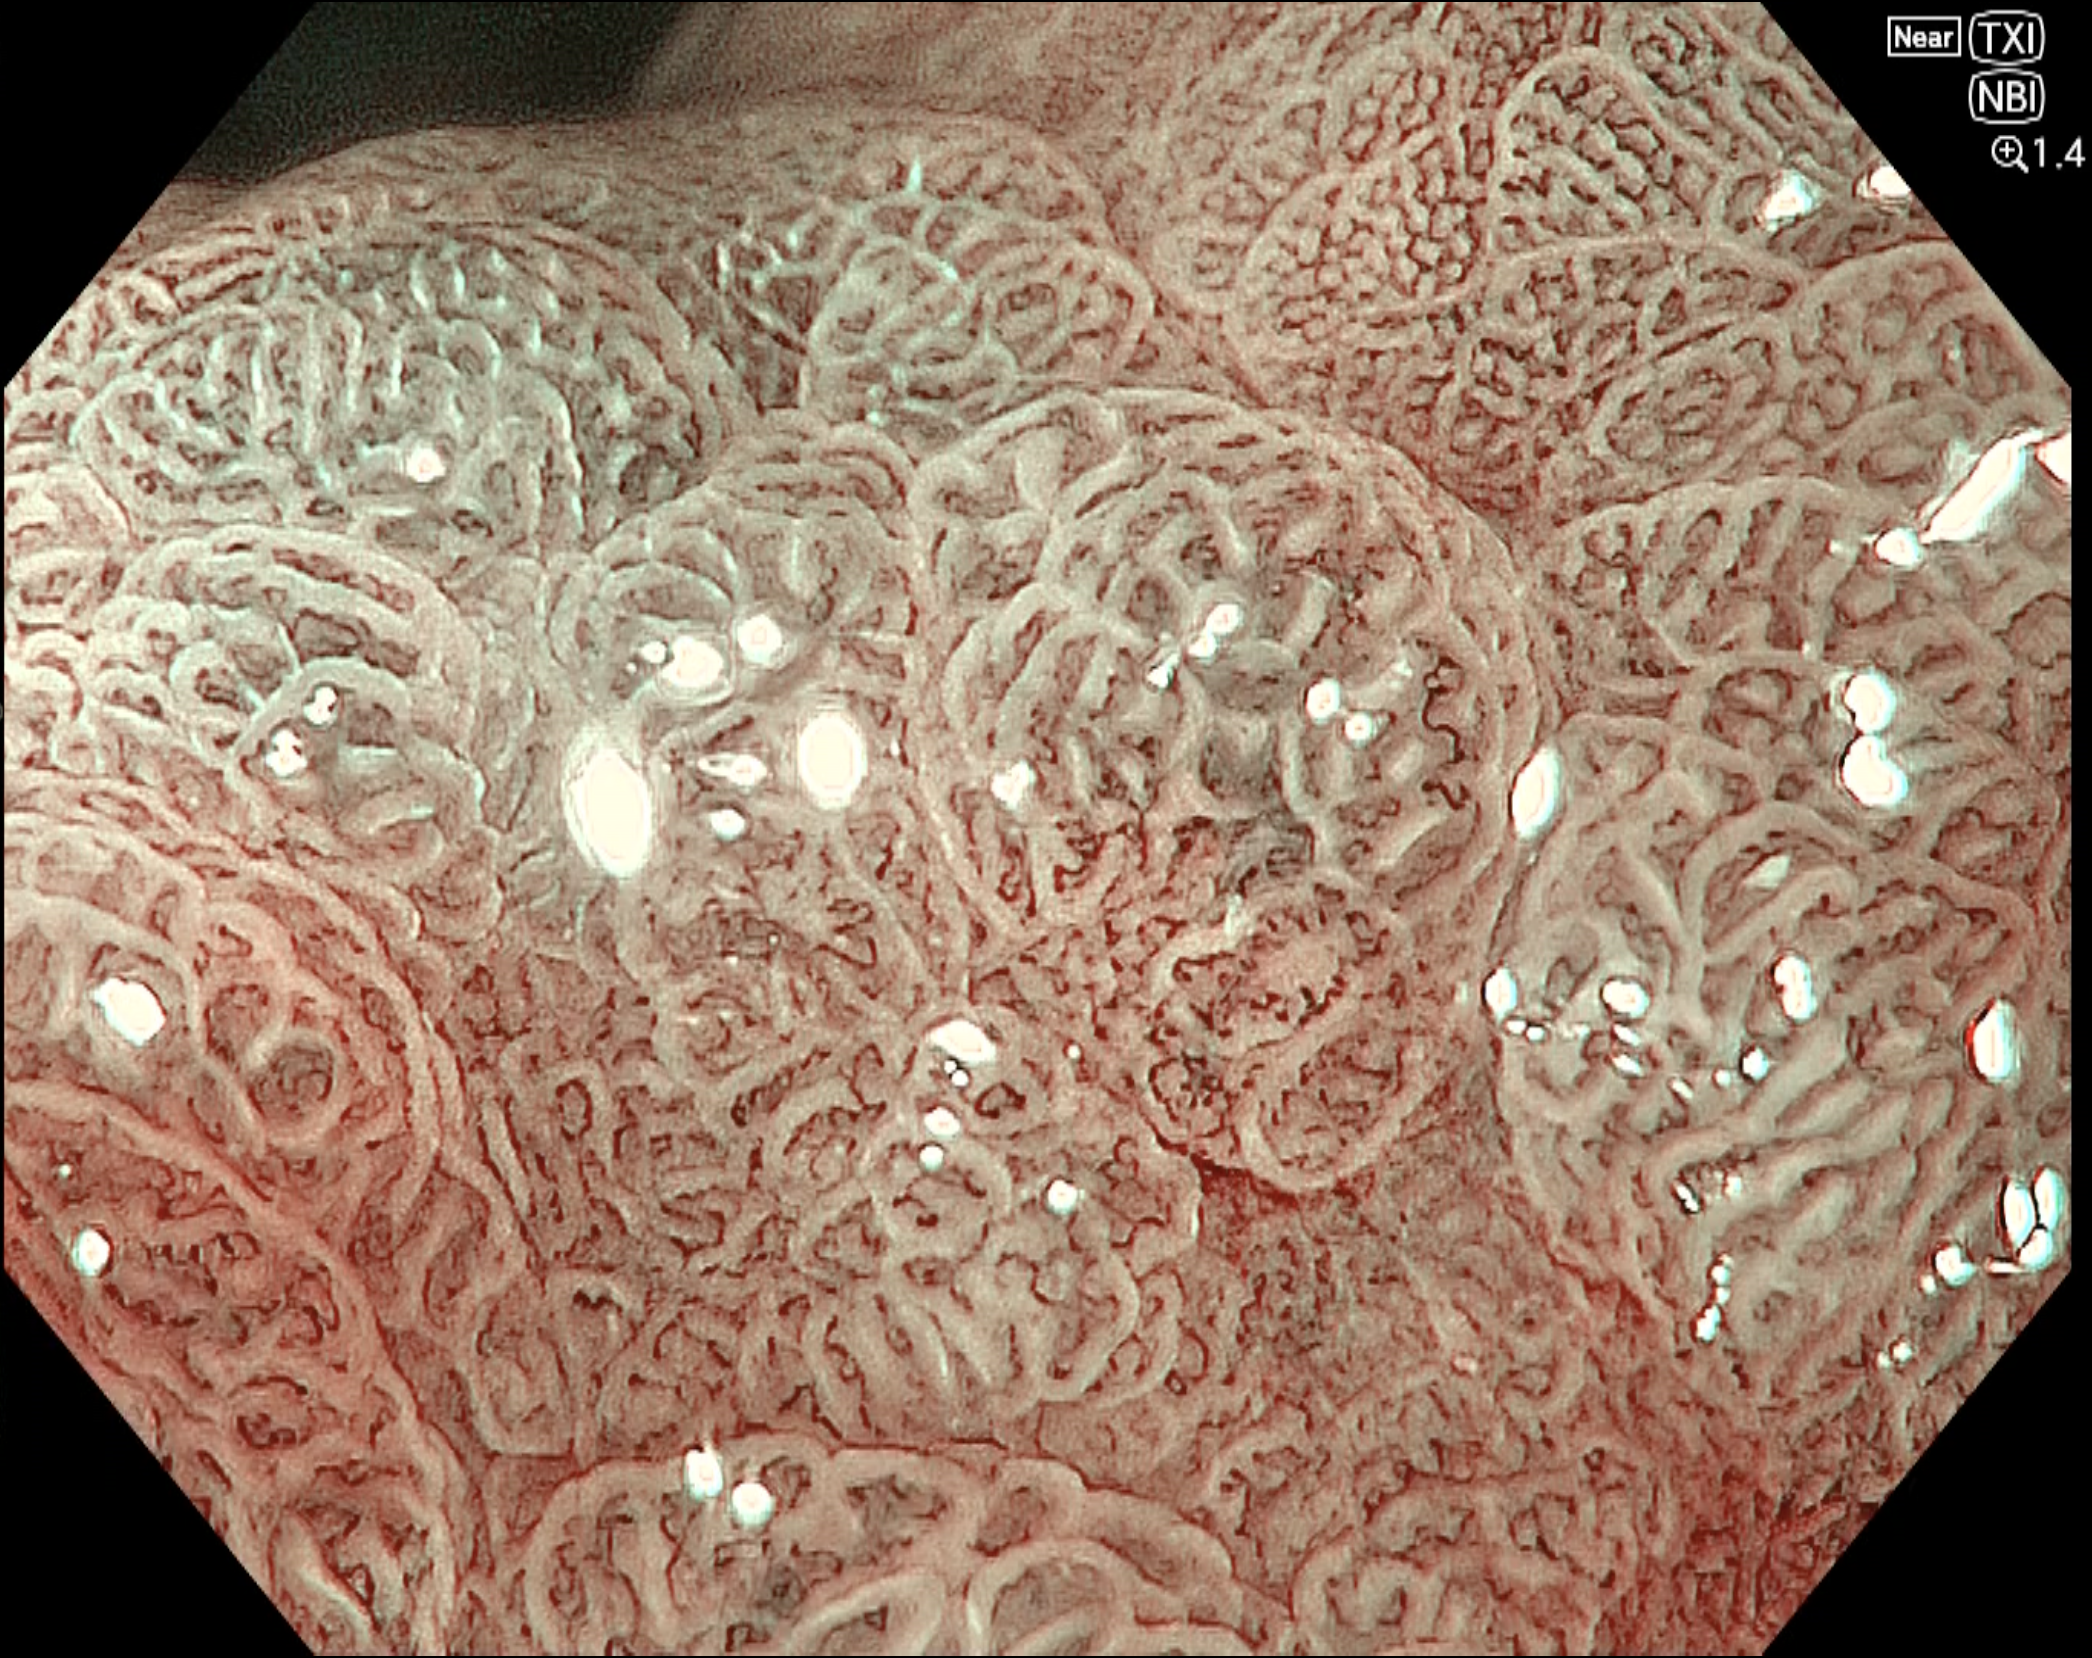

• NBI+TXI観察(電子拡大)

切替前 NBI強調設定:B8

NBI+TXIレベル:高

図9

NBI+TXIモードでは、背景粘膜に緑色の腸上皮化生を疑う所見(light blue crest を伴う green epithelium)を認め、腫瘍部の brownish area との色調差が相対的に強調されていた。また、表面構造の輪郭が明瞭に見えるため、従来のNBI観察と比較して、病変の境界や不整な腺管構造をより認識しやすい。肛門側同様に高分化型腺癌を示唆する所見である。